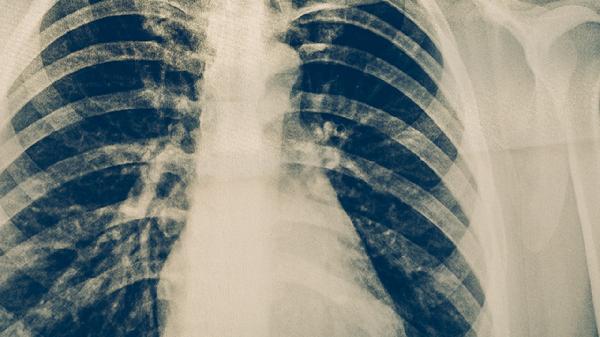

肺結核的早期兩大癥狀主要是咳嗽咳痰和低熱盜汗。肺結核是由結核分枝桿菌感染引起的慢性傳染病,早期癥狀可能較輕但具有提示性,需結合影像學檢查和痰液檢測確診。

持續(xù)兩周以上的咳嗽是肺結核最常見的早期表現,初期多為干咳或少量白色黏液痰。隨著病情進展可能出現黃綠色膿性痰,部分患者痰中帶血絲??人栽诔科鸹蛞归g平臥時加重,可能與支氣管分泌物積聚有關。若合并支氣管結核,可能伴隨刺激性嗆咳或呼吸困難??人园Y狀易與普通呼吸道感染混淆,但肺結核的咳嗽往往遷延不愈,常規(guī)抗感染治療無效。

午后或傍晚出現的低熱是肺結核典型癥狀之一,體溫多在37.5-38℃之間波動,伴有面部潮紅和夜間盜汗。發(fā)熱機制與結核菌釋放的致熱原及機體免疫反應相關。盜汗表現為入睡后大量出汗致衣物浸濕,多發(fā)生在凌晨,與自主神經功能紊亂有關。部分患者僅表現為持續(xù)疲倦感或不明原因體重下降,這些非特異性癥狀常被忽視。發(fā)熱癥狀使用普通解熱藥效果不佳,需抗結核治療才能緩解。